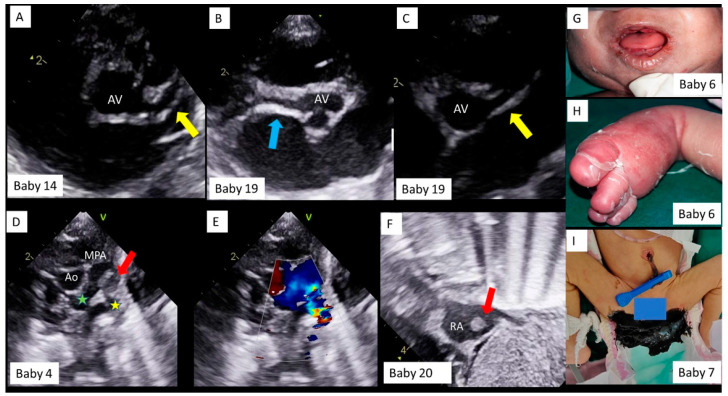

The most common presentation involved the cardiovascular system (Table 3). Eleven had rhythm disorders, of which nine presented with prolonged QTc interval with 2:1 AV block (Figure 2A,D,G,J,M). With immunomodulatory therapy with methylprednisolone and intravenous immunoglobulin (IVIG), 2:1 AV block disappeared first (Figure 2B,E,H,K,N), followed by normalization of QTc (C, F, I, L, O), in all of the nine neonates. One neonate had an episode of supraventricular tachycardia (SVT), requiring a short course of beta blockers, and one infant had bradycardia with tall, peaked T waves and broad QRS due to hyperkalemia secondary to acute renal failure. Shock with or without cardiac dysfunction on echocardiography was seen in five neonates. Two neonates had significant coronary dilatation on day one of life (Figure 3A–C). One neonate had a thrombus almost completely occluding the left pulmonary artery (LPA) (Figure 3D), requiring systemic thrombolysis with Alteplase (t-PA, 3 doses), and low molecular weight heparin (LMWH) for six weeks. One neonate had an intracardiac thrombus at the inferior vena cava–right atrial junction (Figure 3E), which partly resolved at discharge, after LMWH therapy.

Figure 3.

Echocardiography and clinical findings in neonates with MIS-C. Baby number sequence is the same as in Table 3. Transthoracic echocardiography, parasternal short axis view in Baby #14 (A) and Baby #19 (B,C). The left main and left anterior descending coronary artery (yellow arrow) and the right coronary artery (blue arrow) are significantly dilated. AV = aortic valve. Transthoracic echocardiography and color doppler, parasternal short axis view in Baby #4 (D), showing aorta (Ao) and main pulmonary artery (MPA) bifurcation, with a large thrombus (red arrow) obstructing the left pulmonary artery (yellow star) origin and causing flow turbulence on color doppler (E), but normal flows across right pulmonary artery (green star). Transthoracic echocardiography subcostal bi-caval view in Baby # 20 (F), showing a thrombus (red arrow) in right atrium (RA). Baby #6, showing oral and muco-cutaneous lesions (G) and, pedal edema and skin peeling (H) and Baby #7 with black, tarry stools (melena, I).